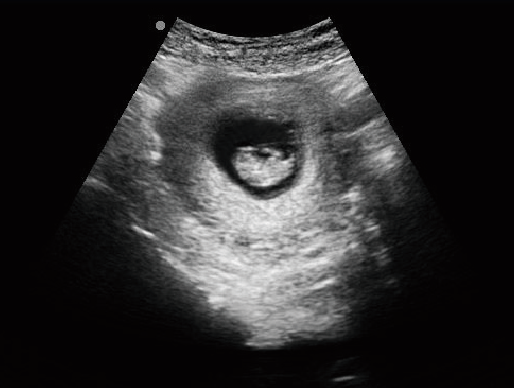

·顯示模式:B、B+B、4B、B+M、M、PW

·適用于各種動物的臨床腹部、胸腔,心臟、肌腱、小器官、眼球、生殖系統等的檢查